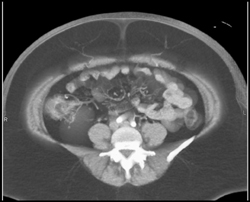

DIEP Protocol Study